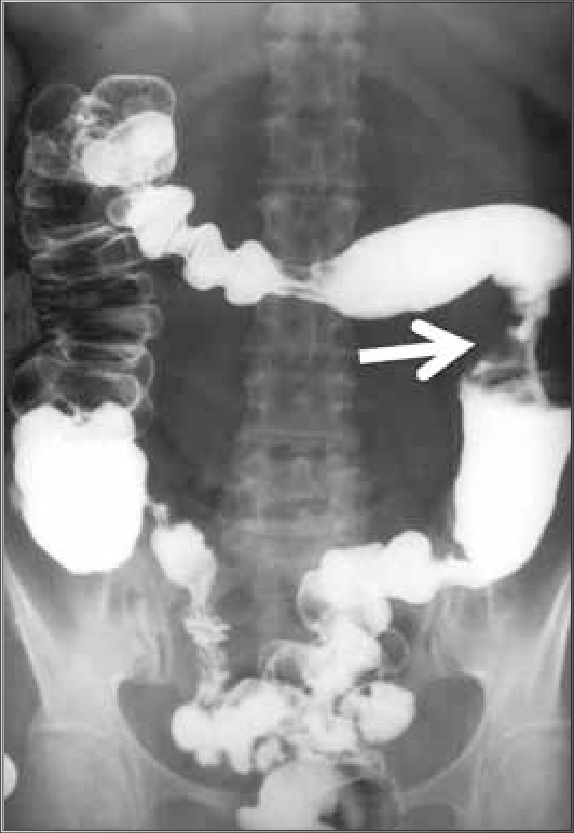

- intussuscepção (0,1 pontos)